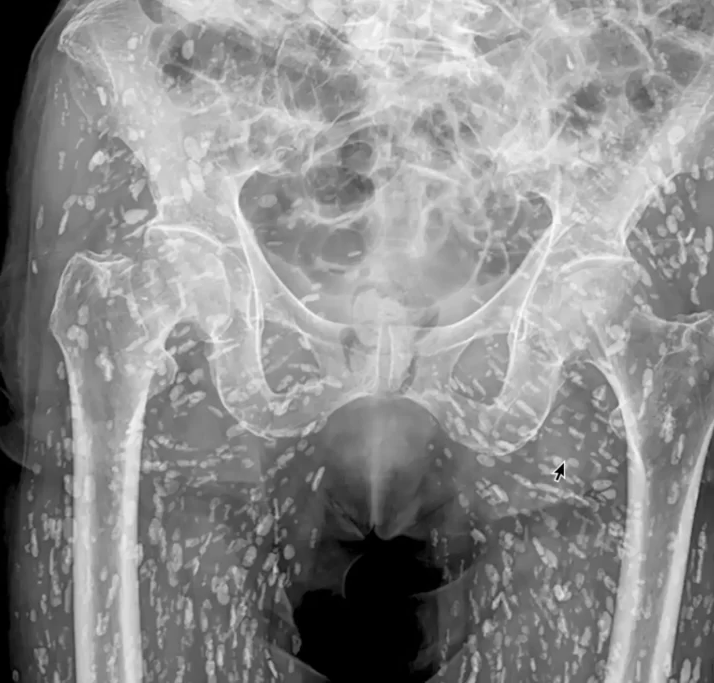

Недавно врач отделения неотложной помощи поделился «одним из самых безумных рентгеновских снимков, которые он когда-либо видел», на котором запечатлена нижняя часть тела человека, кишащая сотнями кальцинированных яиц ленточных червей.

Сэм Гали, врач скорой помощи, специализирующийся на сердечно-сосудистых неотложных состояниях и неотложной радиологии, недавно поделился необычным рентгеновским снимком тазовой области пациента, на котором было видно, что его тело усеяно сотнями белых пятен. Все это были кальцинированные яйца ленточных червей, застрявшие в мягких тканях нижней части его тела. Интересно, что пациент никогда не знал о своем цистицеркозе и узнал об этом только тогда, когда пришел на рентген после падения и боли в бедре.

«Это состояние известно как цистицеркоз, по сути, это личиночные кисты taenia solium, также известного как свиной цепень», — сказал Гали в X (Twitter). «Эти кисты могут перемещаться по всему телу, особенно в мышечные и мягкие ткани бедер и ног».

Пока они не попадут в мозг, эти кальцинированные яйца в основном безвредны, они больше нежизнеспособны, но если сама мысль о том, что вы можете быть заражены сотнями этих цист, похожих на рисовые зерна, кажется вам невообразимой, вам следует воздержаться от сырой или недоваренной свинины и рыбы, просто чтобы обезопасить себя.